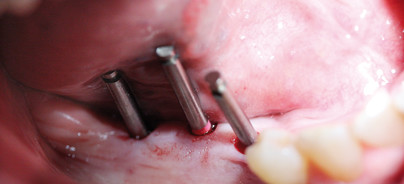

Foto: Minimalinvasive Implantation bei multiplen Exostosen

Da die Patientin bereits im letzten Jahr erfolgreich in Regio 25 mit einem minimalinvasiv implantierten K.S.I. Bauer-Implantat versorgt wurde, entschieden wir uns für eine weitere Implantationsversorgung. Das reduzierte Knochenangebot, bedingt durch eine extreme bukkale Atrophie in Regio 47–45, wurde durch die Exostosen ausgeglichen. Die Kieferkammbreite von 7,5mm ermöglichte eine trans-gingivale Implantation. Mit einer Stanze von 4mm Durchmesser wurden drei Gingivastanzungen vorgenommen. Die erste Pilotbohrung mit dem grazilen K.S.I. Pilotbohrer „gelb“ wurde 10mm tief durchgeführt. Ein OPG gab Aufschluss über Tiefe und Lage des Bohrloches. Entsprechend der Bohrsequenz wurden zwei weitere Bohrungen durchgeführt und drei einteilige A-Implantate aus dem K.S.I. Bauer-System mit 4,1mm Durchmesser und 8, 10 und 12mm Länge inseriert. Aufgrund starker lingualer Knocheneinziehungen waren längere Implantate nicht einsetzbar. Unmittelbar nach der Implantation konnte ein Doppelabdruck mit Übertragungskappen für die definitive Kronenversorgung genommen werden. Als provisorische Versorgung wurde eine Kunststoffschiene über die drei Implantatköpfe gesetzt. Durch diese Verblockung wurde die Ruhigstellung erreicht. Da weder Knochenresorptionen noch Gingivarezessionen zu erwarten waren, konnte die Gerüstanprobe sowie Fertigstellung innerhalb von nur zehn Tagen nach Implantation erfolgen.